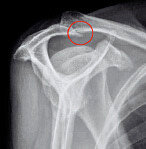

운동하다 다친 부위 ‘통증 퇴장!’

스포츠를 심하게 하면 운동이 아니라 ‘고문’이 된다는 말이 있다. 자신의 운동 능력과 몸 상태를 고려하지 않고 과도하게 하는 스포츠는 운동이 아니라 병을 만드는 원인이 될 수 있다는 뜻이다. 관절과 인대, 힘줄, 근육 등 인체의 운…

휴가 중 ‘삐끗’ 방치하다 탈 날라

달콤하게 보낸 휴가가 후회로 남는 건 후유증 때문이다. 특히 여름휴가는 건강을 해치는 요소가 여기저기 있어 일상 복귀에 어려움을 겪는 사람들이 많다. 게다가 레저의 유형이 다양해지고 과격해져 휴가 중 코 부상, 치아 손상, 인대 파…